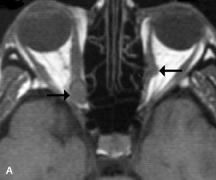

Breast carcinoma metastatic to the orbit has been demonstrated to be hypointense to the surrounding orbital fat on T1-weighted studies and hyperintense on T2-weighted images and has an affinity to the extraocular muscles (Fig. 20).50,64 The MRI characteristics of prostate carcinoma metastatic to the orbit have been described as involving the greater and lesser wing of the sphenoid, orbital roof, and optic canal. Diffuse bone hypertrophy with isointense or slightly hyperintense tissue on T1-weighted images represents the osteoblastic carcinomatous bone infiltration. Contrast enhancement is variable on T1-weighted and fat-suppressed images.65

Fig. 20. A. T1-weighted MR scan demonstrates nodular enlargement of both medial rectus muscles (arrows). B. T1-weighted fat-suppressed contrast-enhanced scan confirms the presence of small metnstatic deposits within the muscles (open arrows).